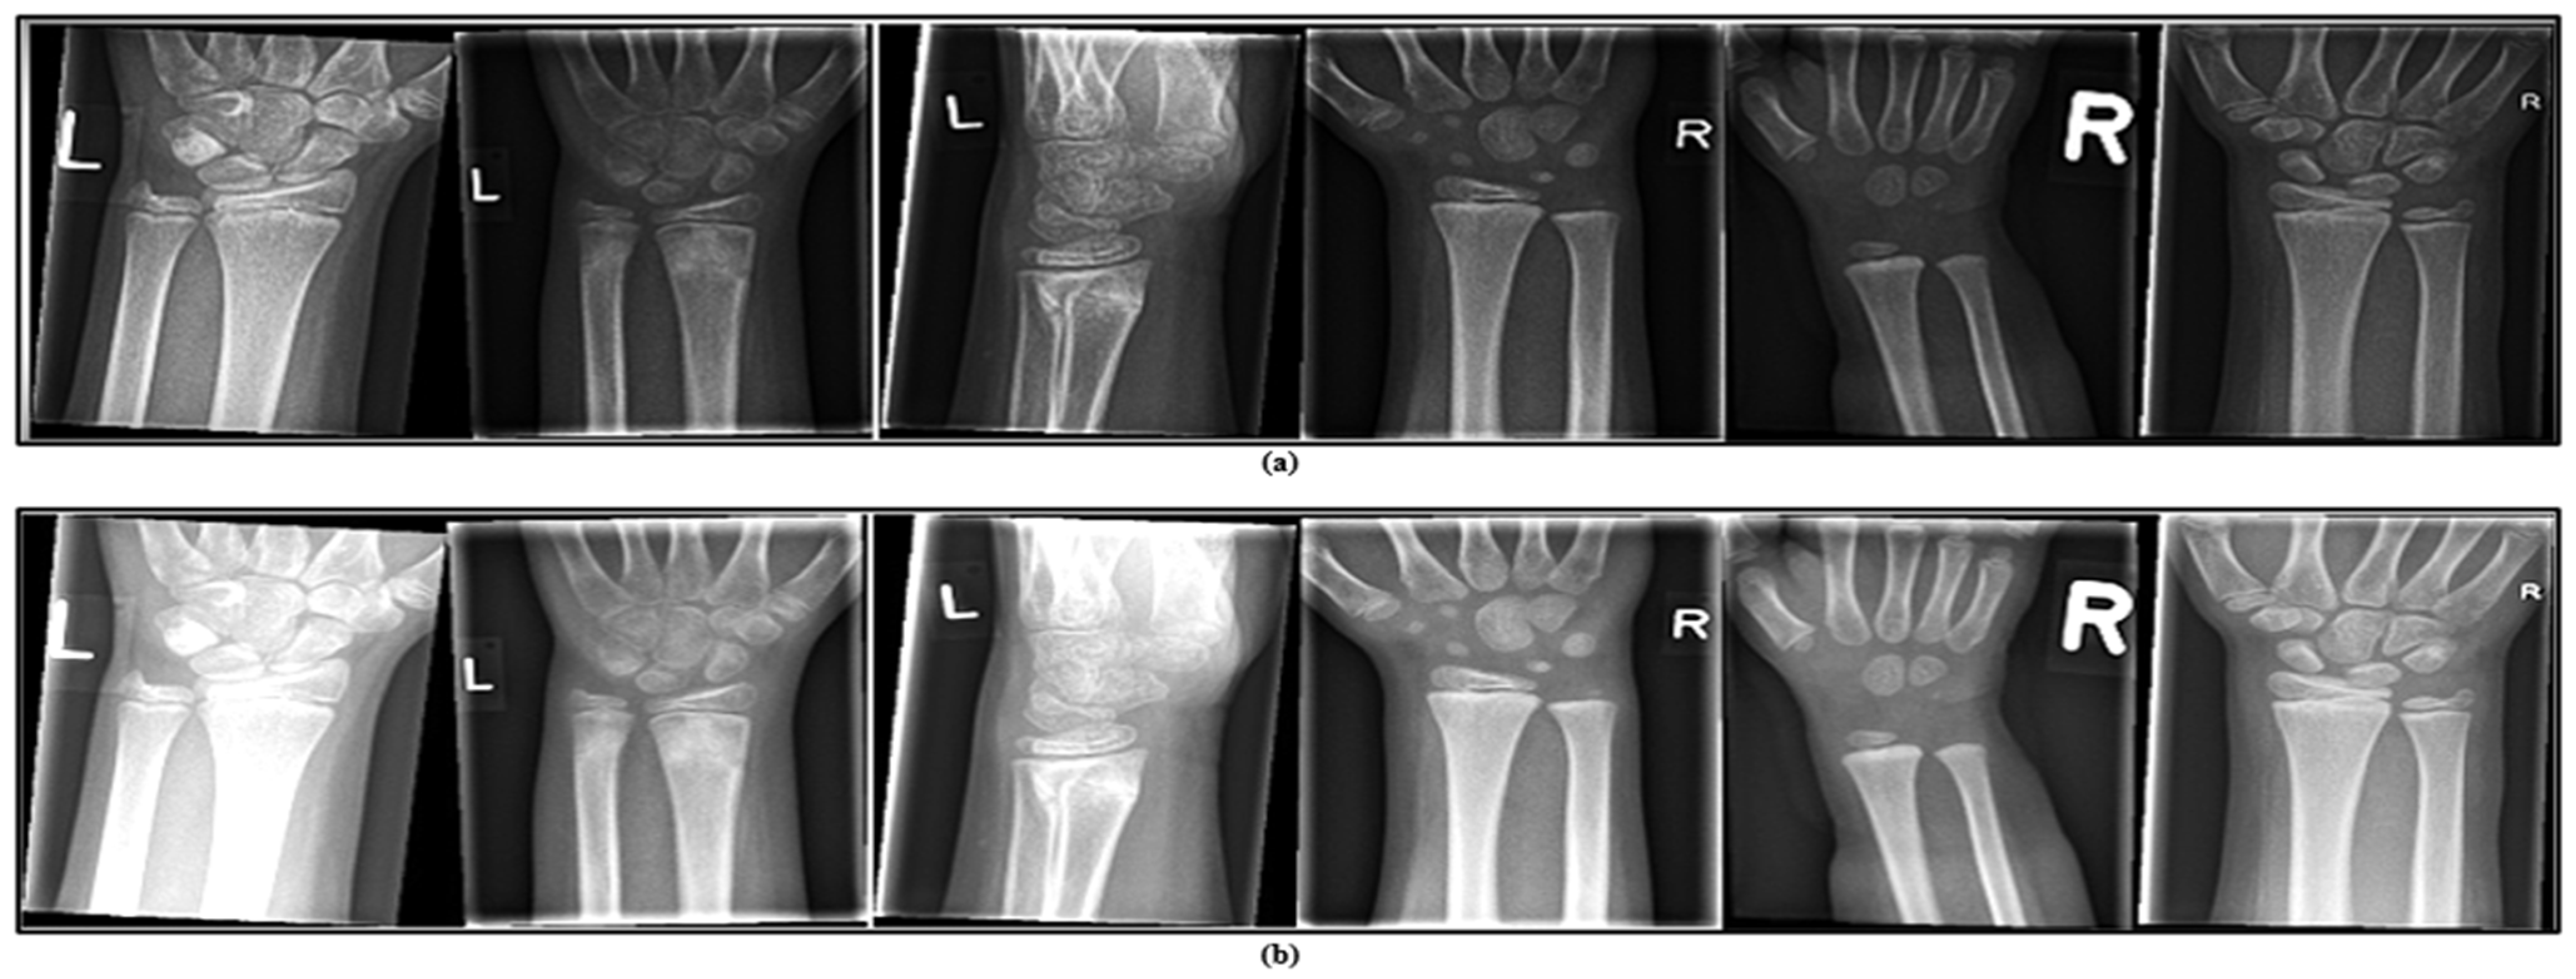

4.1. Dataset

- This dataset is general, containing 20,327 labelled and categorized images, and is ideal for developing and testing computer vision models.

- The dataset includes a wide variety of images capturing early bone development in children.

- Reviewing wrist development at this stage provides important insights for identifying, managing, and preventing abnormalities that might not be noticeable in adult wrists.